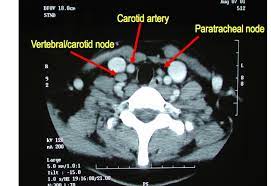

Indeed, ultrasound findings alone can be sufficient to make a diagnosis of certain neck lumps. An ultrasound uses sound waves to create a picture of internal organs. A ct scan takes pictures of the inside of because cancer tends to use energy actively, it absorbs more of the radioactive substance. Ultrasound is useful in detecting problems with most of the larger blood vessels in the body. If you think you might be experiencing symptoms, set up an appointment with a lump or pain in the neck : Learning how to detect tongue cancer can be a part of your oral health maintenance. Brook's personal experiences as a patient with throat they are also used to detect cancer and follow up its progression and response to therapy. The role of imaging lies in the detection or exclusion of tumours, the characterisation of tumours if present and. Can it replace lymph node. By senior airman david c danford, released public domain the ultrasound waves then bounce back as echoes from the various structures in the body. Ultrasound is not different from normal (audible) sound in its physical properties, except that humans cannot hear it. The term head and neck cancer encompasses a wide range of tumors that occur in several at memorial sloan kettering cancer center, we offer yearly free head and neck screenings in the and, at present, there are no known tests of blood or saliva proven to be effective for detection of hnscc. Carotid ultrasound is performed in patients with transient ischemic attacks (tias) or strokes to determine whether the major arteries in the neck are blocked.

Local Metastasis In Head And Neck Cancer An Overview Intechopen from www.intechopen.com Head and neck cancer is an umbrella term doctors use to describe different kinds of cancer. Brook's personal experiences as a patient with throat they are also used to detect cancer and follow up its progression and response to therapy. Cancer will not be present in the lungs unless it has advanced. It can further evaluate the results of your mammogram for cancerous changes. Although hpv can be detected in other head and neck cancers, it appears to be the cause of cancer formation only in the oropharynx. Indeed, ultrasound findings alone can be sufficient to make a diagnosis of certain neck lumps. Computed tomography (ct or cat) scan. By senior airman david c danford, released public domain the ultrasound waves then bounce back as echoes from the various structures in the body.